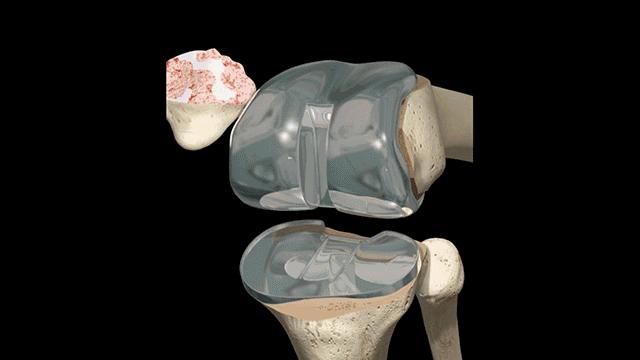

所以年纪比较大的朋友,出现膝盖疼痛及活动时总发生响声时,可以要到关节外科照一个X光,最好是双下肢站立位的全场片,能够看到膝关节的力线和磨损情况。轻度的,行保守治疗(注射透明酸钠,口服软骨补充剂,功能康复锻炼等),重度患者,需要进行全膝关节成形术。

膝关节置换过程